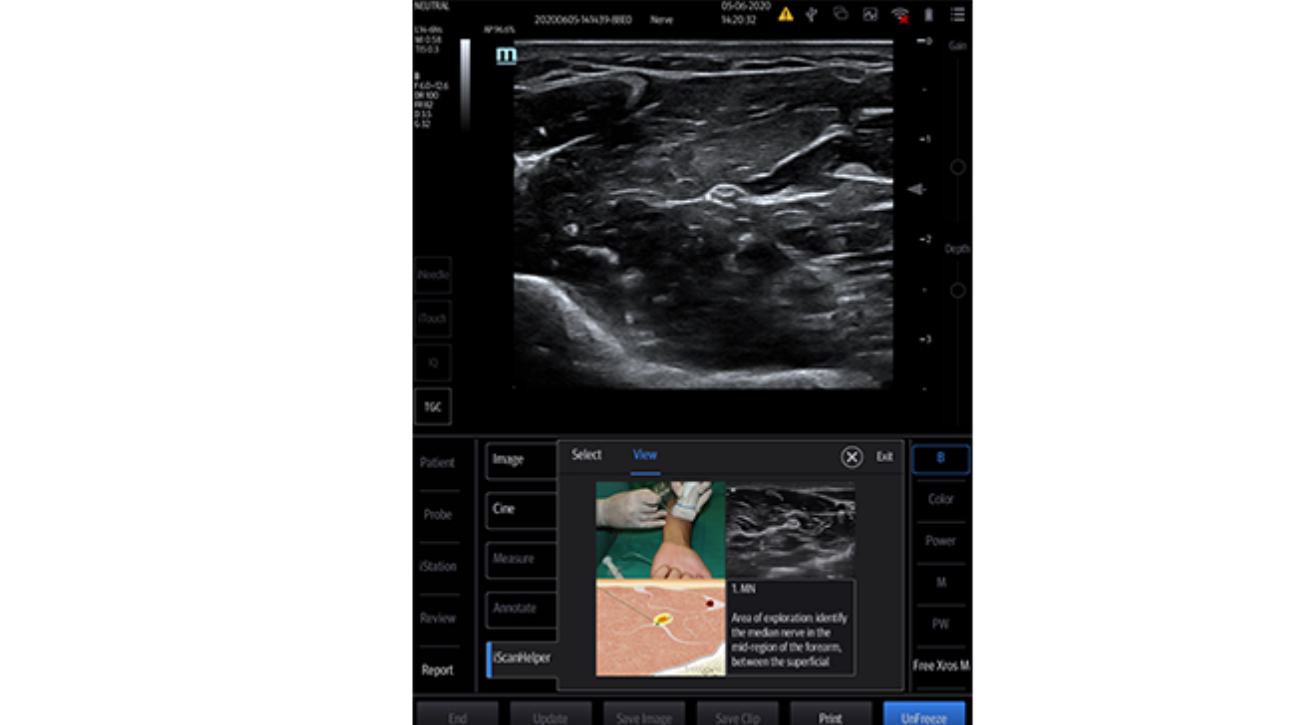

With its superior image quality, simple touchscreen operation and class-leading intelligent tools, the Mindray TE7 ACE is designed to simplify and speed-up ultrasound examinations.

Its versatility makes it suitable for demanding point-of-care environments including Critical Care, Emergency and Anaesthetics.